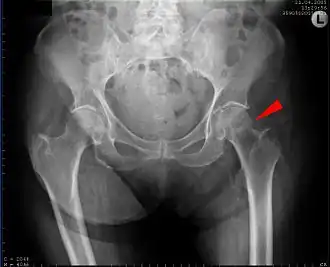

Vrijwel altijd wordt de diagnose duidelijk door een röntgenfoto. Omdat de patiëntes (of patiënten) ouder zijn en vrijwel altijd geopereerd moeten worden, zal preoperatief onderzoek gedaan worden. Er wordt bloed afgenomen, een longfoto gemaakt en een elektrocardiogram. Soms worden ook andere artsen van andere specialisaties in consult gevraagd voor medebehandeling.[1]

Collumfractuur

De collumfractuur kan volgens de Garden-classificatie worden onderverdeeld in: niet-gedislokeerd (Garden type 1 en 2) en gedislokeerd (Garden type 3 en 4).

In de meeste gevallen zal er bij een niet-gedislokeerde collumfractuur, gekozen worden voor osteosynthese. Hierbij worden de botdelen aan elkeer gezet door middel van osteosynthesemateriaal zoals de glijdende heupschroef (GHS) of gacannuleerde schroeven.

De gedislokeerde collumfractuur (Garden type 3 en 4) kan zowel worden behandeld door middel van een osteosynthese of door middel van een endoprothese. Deze keuze is afhankelijk van de leeftijd van de patiënt en de lichamelijke en geestelijke conditie. Wanneer er gekozen wordt voor een osteosynthese zal eerst de heupkop weer recht op het dijbeen gezet moeten worden, dit heet repositie. Als deze stand gelijk is aan de normale stand kan er gebruik worden gemaak van osteosynthesemateriaal. Als repositie niet of onvoldoende lukt wordt er alsnog gekozen voor een endoprothese.[1]